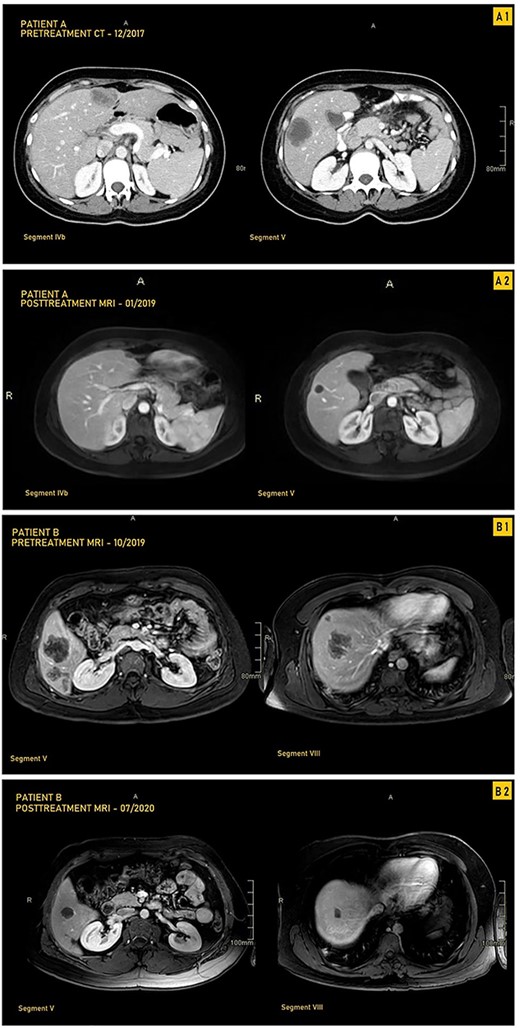

CT and MRI images our two patients before and after treatment with pembrolizumab; (A1) Pretreatment MRI of our first patient in September 2017 showing most prominent lesions, located in Segments IVb and V, on axial enhanced CT after contrast administration; (A2) Posttreatment axial enhanced T1-weighted MRI of our first patient in January 2019 showing most prominent lesions located in Segments IVb and V; the lesion in Segment V is smaller, measuring 1.4 cm, and is completely necrotic; (B1) Pretreatment axial enhanced T1-weighted sequence MRI performed on 3Tesla field strength following gadolinium contrast administration in our first patient in October 2019 showing most prominent lesions, located in Segments V and VIII; the largest metastatic lesion is a 4.8-cm heterogeneously enhancing metastatic lesion in Segment VIII; (B2) Posttreatment axial enhanced T1-weighted sequence MRI performed on 3Tesla field strength following gadolinium contrast administration in the hepatobiliary phase in our second patient in July 2020, showing most prominent lesions located in Segments V and VIII; the largest lesion in Segment VIII decreases in size to 1.5 cm following treatment and is completely necrotic.

A 33-year-old male patient was diagnosed with adenocarcinoma of the transverse colon with 24 bilobar hepatic metastases. He was started on four cycles of Xelox and Avastin after which some lesions responded to treatment while others did not, as evidenced by changes in the hepatic lesions on magnetic resonance imaging (MRI) (Fig. 1B1 and Table 1). Immunohistochemical analysis showed loss of MLH1 and PMS2 with retention of MSH2 AND MSH6; he was started on pembrolizumab (12 cycles) with consistent interval decrease in size of both the colonic mass and hepatic lesions over several follow-ups every 3 months (Table 1). After multiple months, MRI showed a marked decrease in the transverse colonic mass and all hepatic lesions which became necrotic; four hepatic lesions became barely visible or disappeared (Table 1 and Fig. 1B2). He underwent a transverse colectomy with primary anastomosis and metastasectomy where all hepatic lesions were negative for residual carcinoma with negative surgical margins and areas of necrosis.